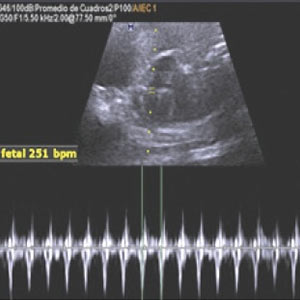

Ecocardiografía fetal: situación actual de diagnóstico en el Hospital Obrero N° 2, CNS Las cardiopatías congénitas constituyen las malformaciones fetales más frecuentes, con una incidencia mundial de 6 a 8 por mil nacidos vivos y 27 por mil nacidos muertos. |